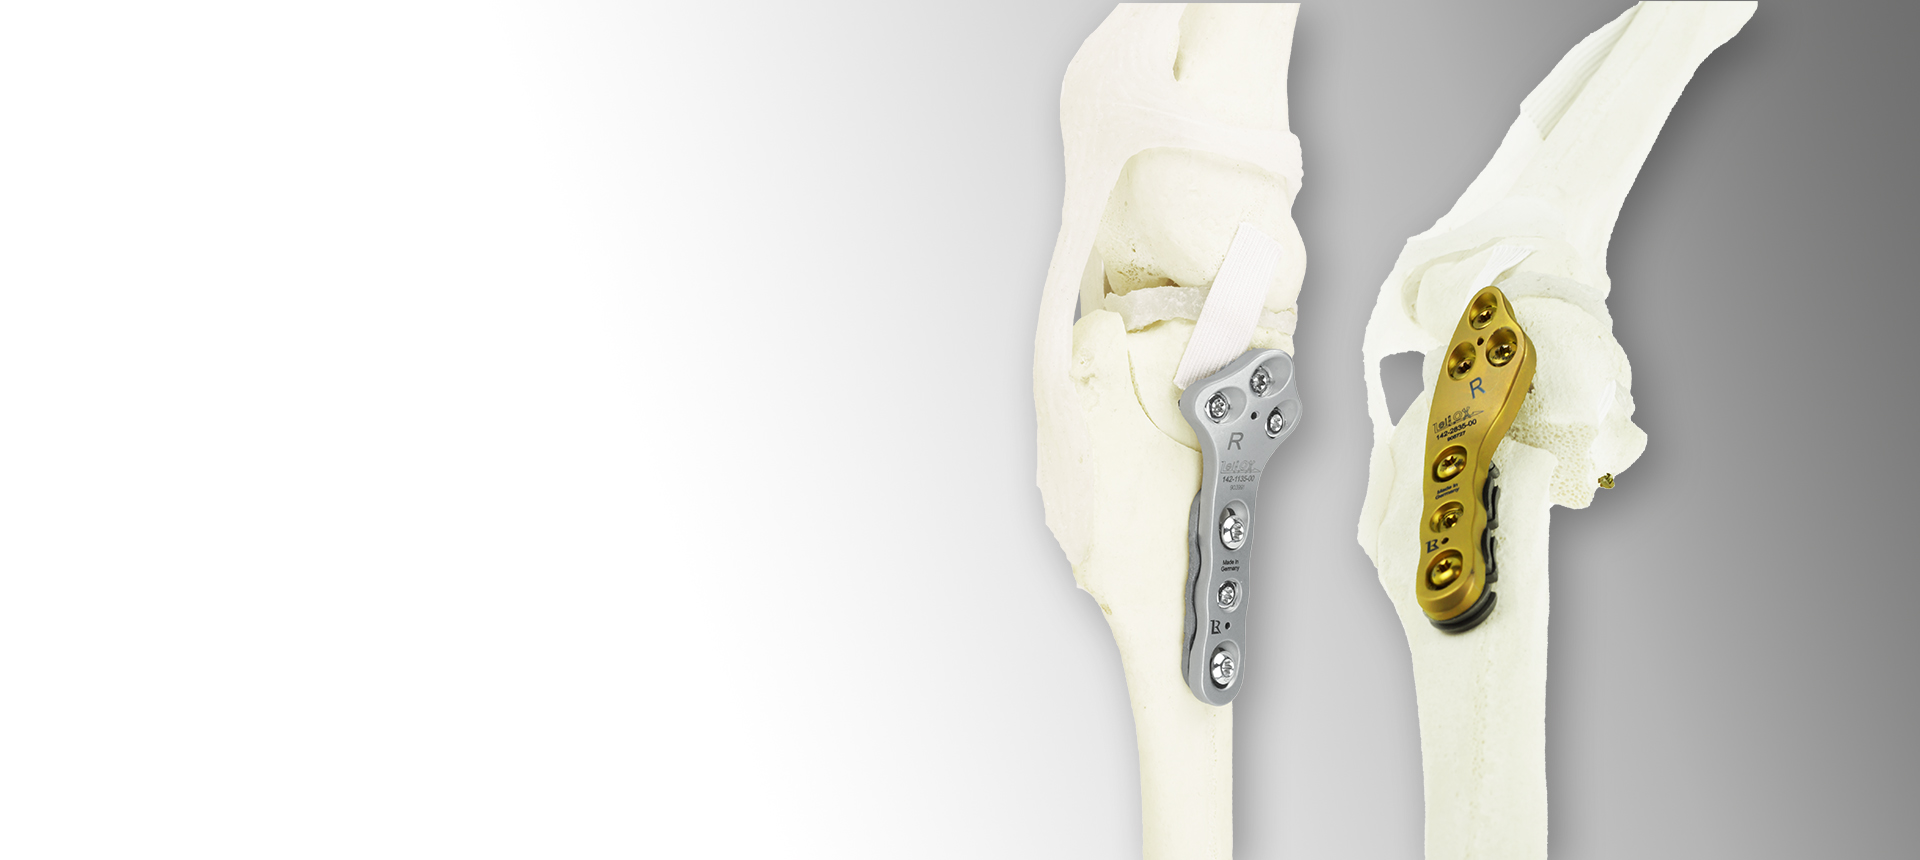

Orthopedic Implants & Veterinary Courses for Animal Surgery

Products

Technology Leading Manufacturing

A Titanium LeiLOX CBLO Plate is born in one of our in-house machines: